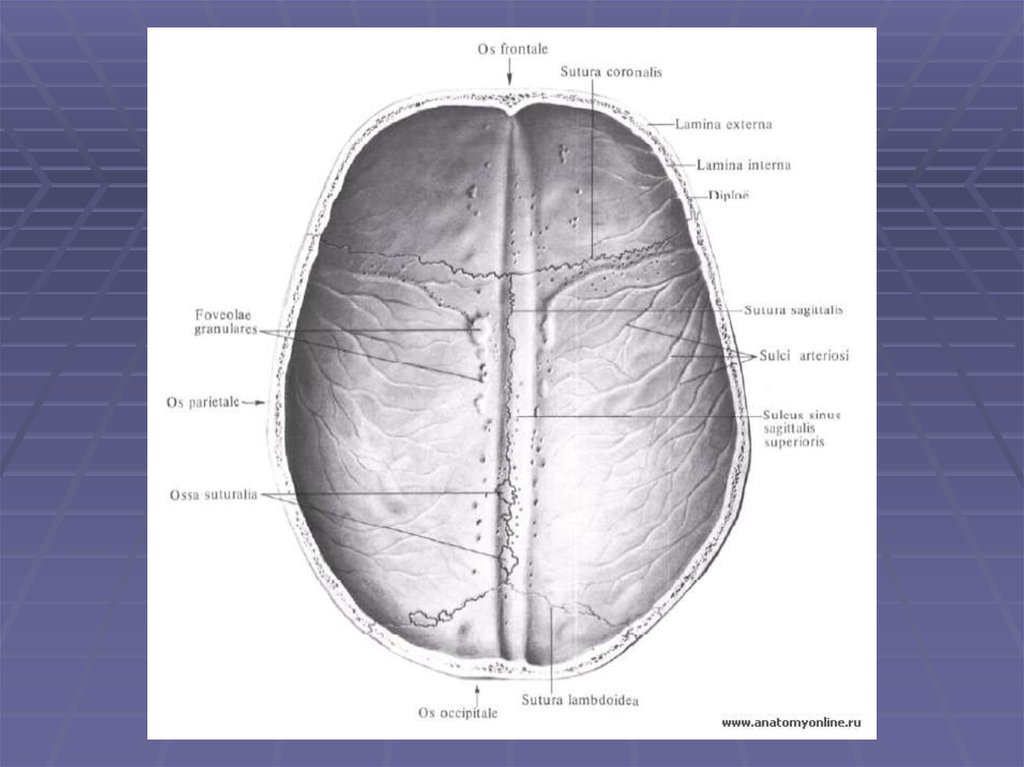

Череп